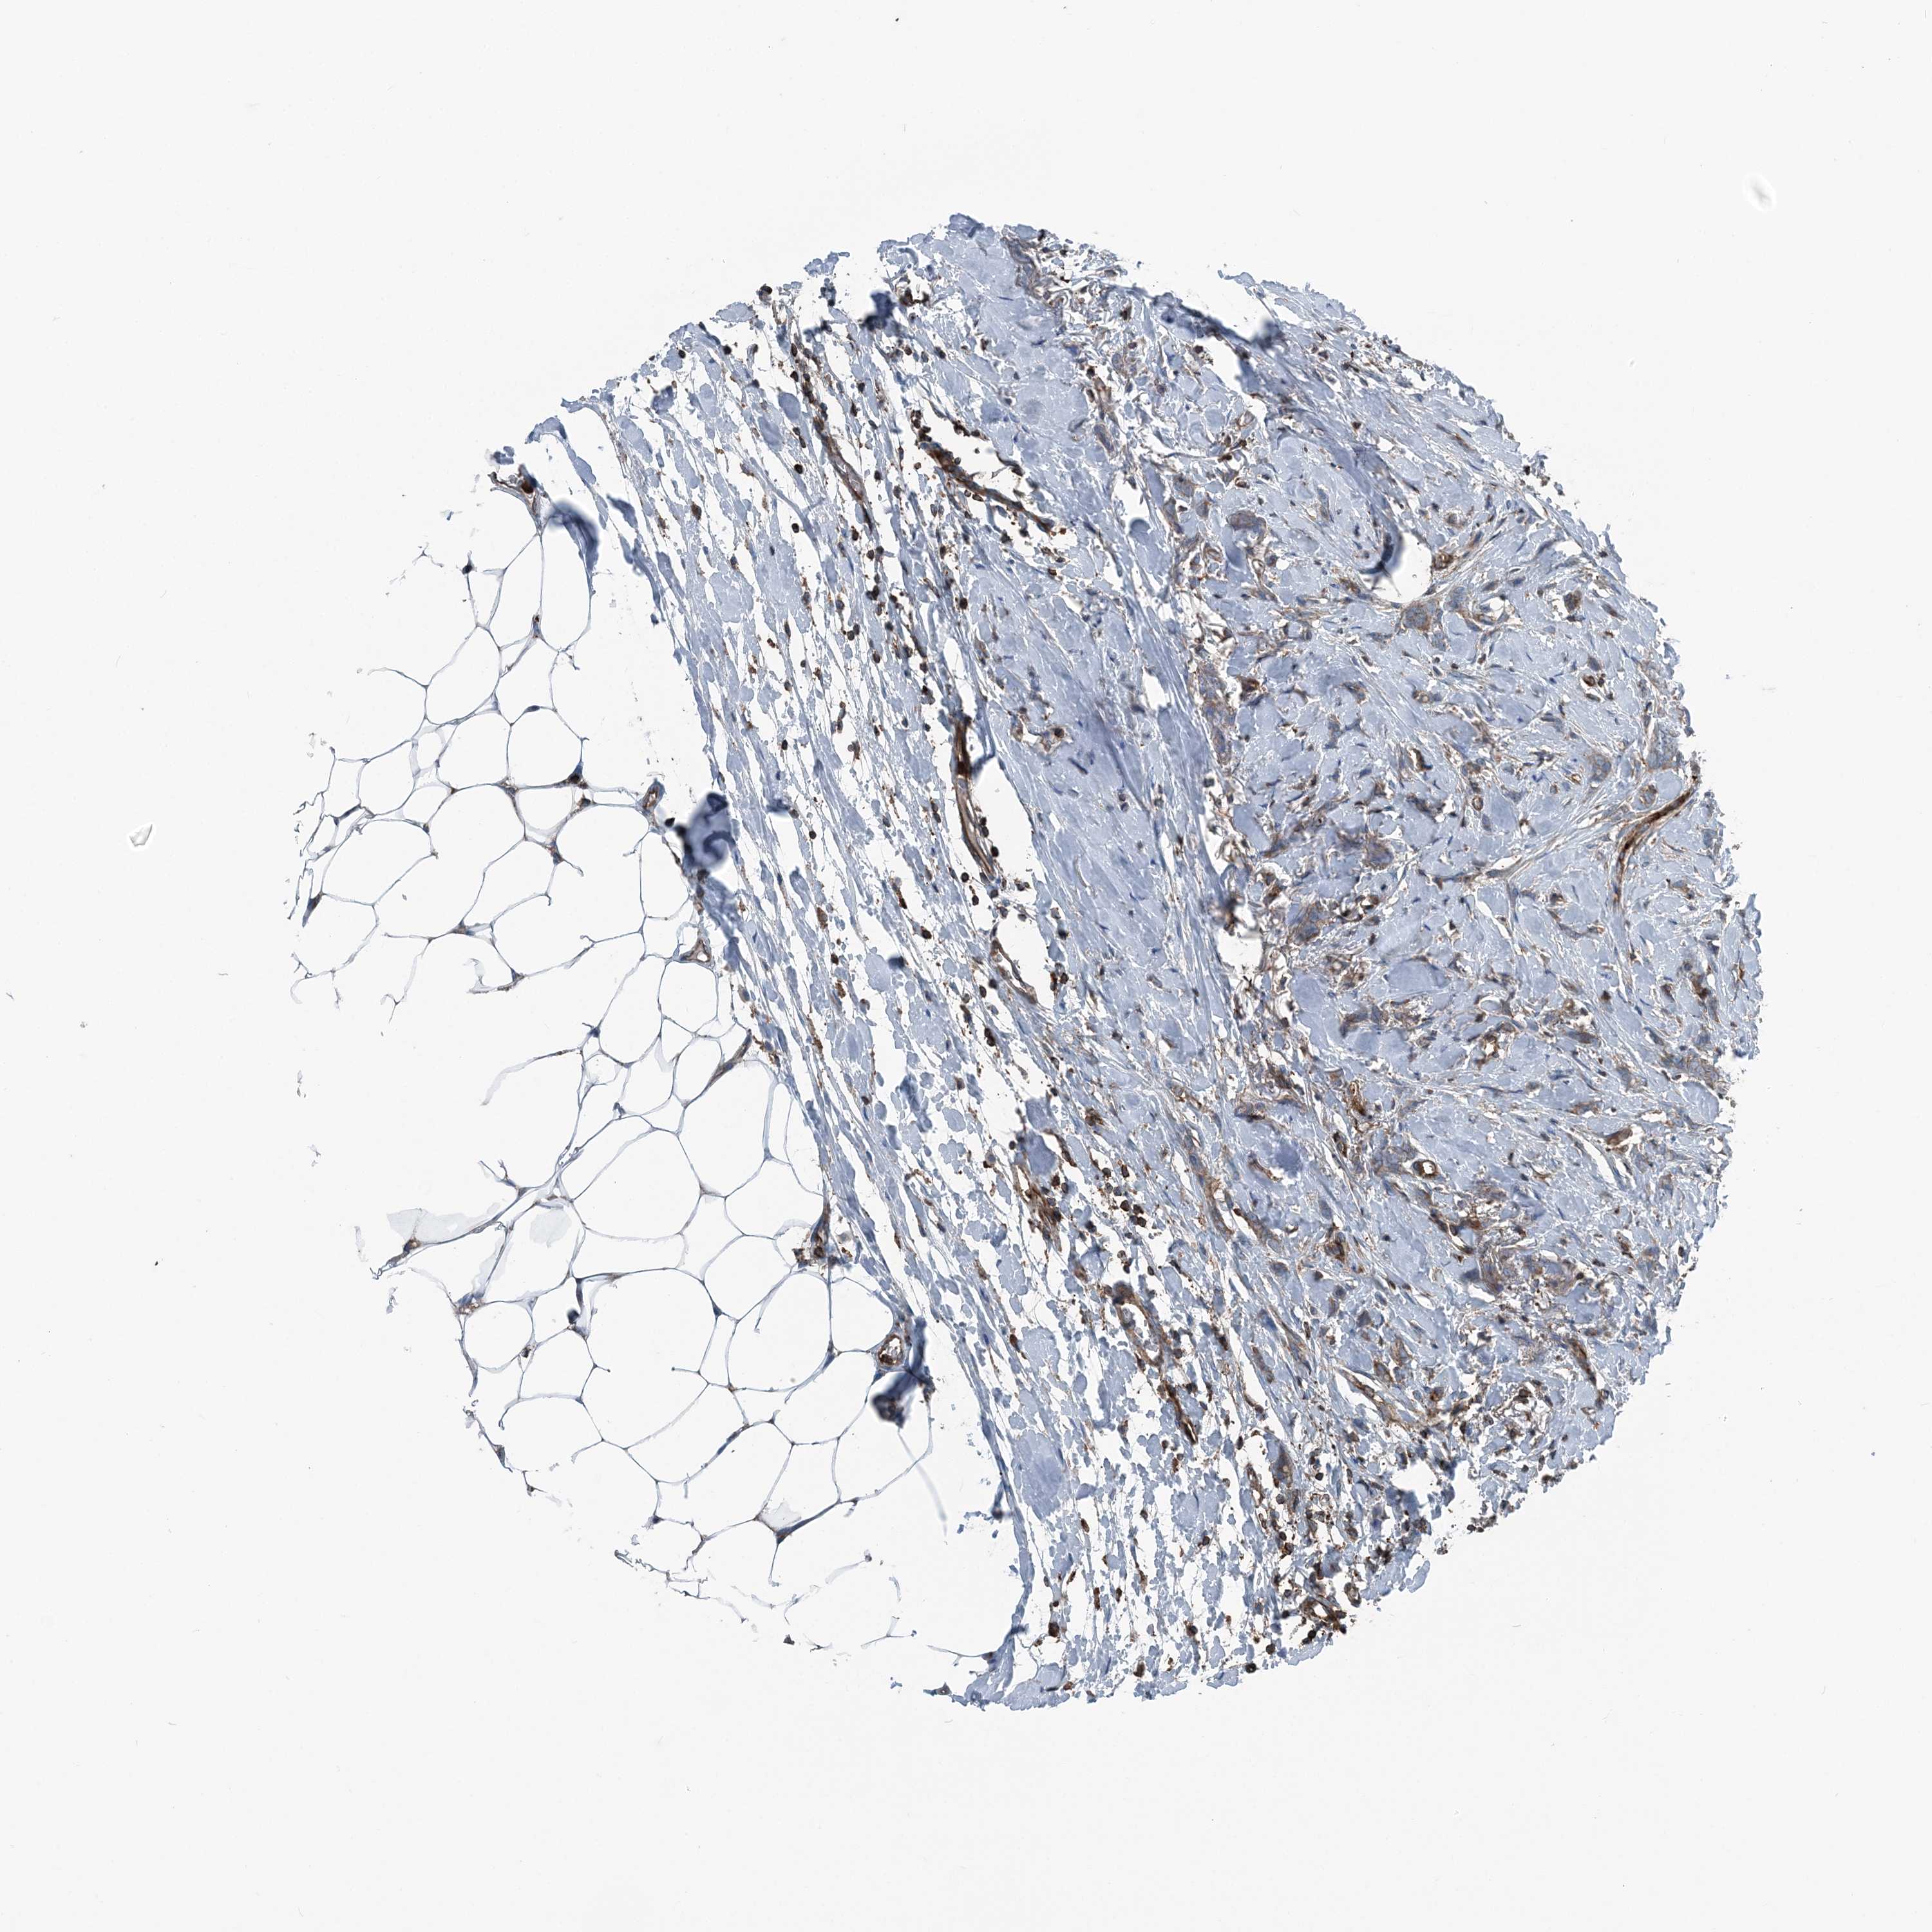

BRCA TCGA BRCA VALIDATION PROTEIN EXPRESSION

ANTIBODIES

AND

VALIDATION